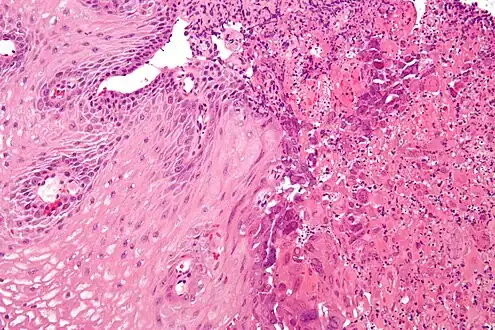

Esophagitis can be diagnosed by upper endoscopy, biopsy, upper GI series (or barium swallow), and laboratory tests.[4]

An upper endoscopy is a procedure to look at the esophagus by using an endoscope. While looking at the esophagus, the doctor is able to take a small biopsy. The biopsy can be used to confirm inflammation of the esophagus.

Laboratory tests can be done on biopsies removed from the esophagus and can help determine the cause of the esophagitis. Laboratory tests can help diagnose a fungal, viral, or bacterial infection. Scanning for white blood cells can help diagnose eosinophil esophagitis.